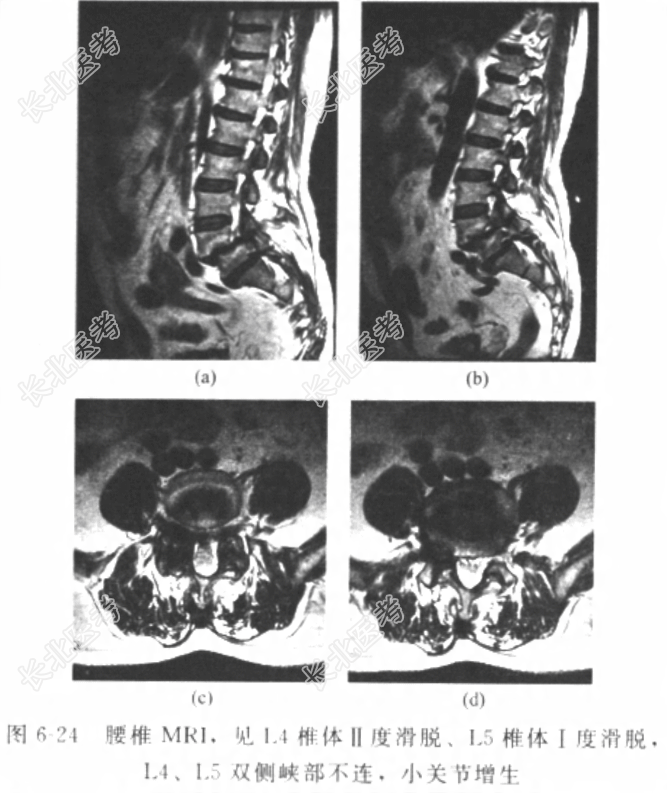

[材料题] 患者男性,50岁,因“反复腰痛二十余年,加重伴右下肢跛行3个月”入院。腰部疼痛二十余年,劳累时加重,休息后缓解。3个月前劳作后腰痛加重,伴有右下肢麻木、疼痛。步行约200m需下蹲休息才能缓解麻木、疼痛。经非手术治疗症状无明显缓解。患者既往体健,否认其他“心、肝、肺、脾、肾”等重要脏器疾病史,否认传染性疾病史,否认外伤史、输血史,否认食物、药物过敏史。体格检查:T37.0℃,P78次/分,R20次/分,BP130/70mmHg。神志清楚,腰椎生理前凸增大,腰3/4棘突间扪及台阶样改变。右大腿后外侧、右小腿前外侧、右足背内侧皮肤感觉减弱,右伸拇趾肌力较对侧稍减弱。右直腿抬高试验,可抬高60°,为阳性,加强试验阳性。辅助检查:腰椎X线片(图6-22)示腰4、腰5椎体前滑脱,腰4及腰5可疑峡部裂。 入院诊断:腰4、腰5滑脱症,腰4、腰5双侧峡部裂。诊疗计划:完善检查,积极术前准备。患者常年从事拉板车、抬石头等重体力劳动,有下腰痛病史二十余年,休息或口服镇痛药缓解。3个月前劳作后腰痛加重,伴有右下肢麻木、疼痛。步行200m需下蹲休息才能缓解。经过休息及外院按摩、理疗等,仍有腰痛伴右下肢麻木、疼痛。无法长距离行走,约200m就需要下蹲休息。患者行腰椎CT三维及MRI检查,如图6-23、图6-24。